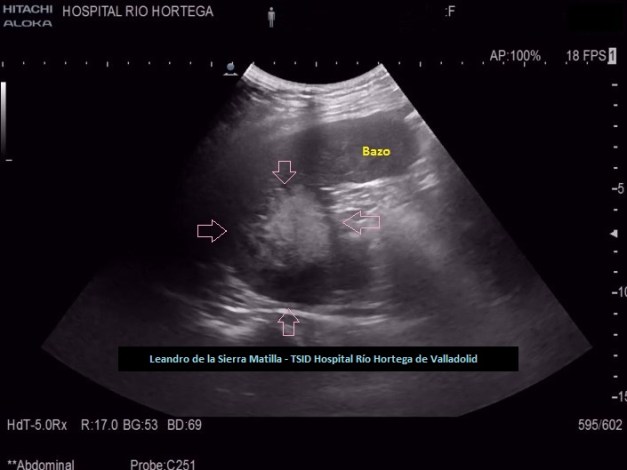

Durante el estudio del peritoneo, retroperitoneo y cadenas linfáticas abdominales, observamos una lesión superficial, redondeada, heterogénea, hipo-Isoecogénica con zonas hiperecogenicas, de aspecto sólido.(FIGURA 4)

4